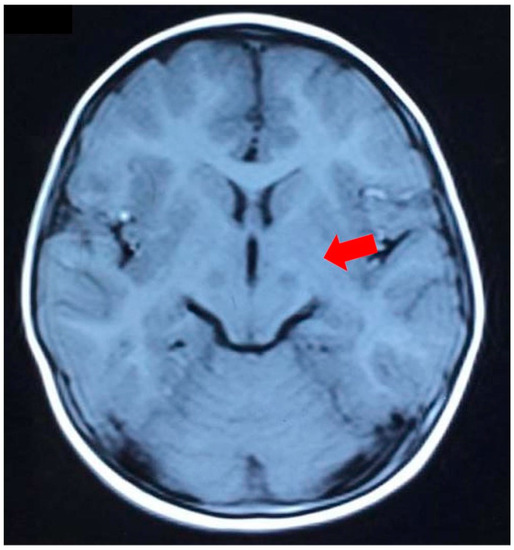

| Brain MRI | Abnormal signal of bilateral thalamus | UNK | Abnormal signal of the bilateral cortical spinal tract | bilateral lesions in the midbrain, thalamus, and dentate body of the cerebellum | Bilateral lesions in the brain stem, thalamus, and dentate body of the cerebellum |